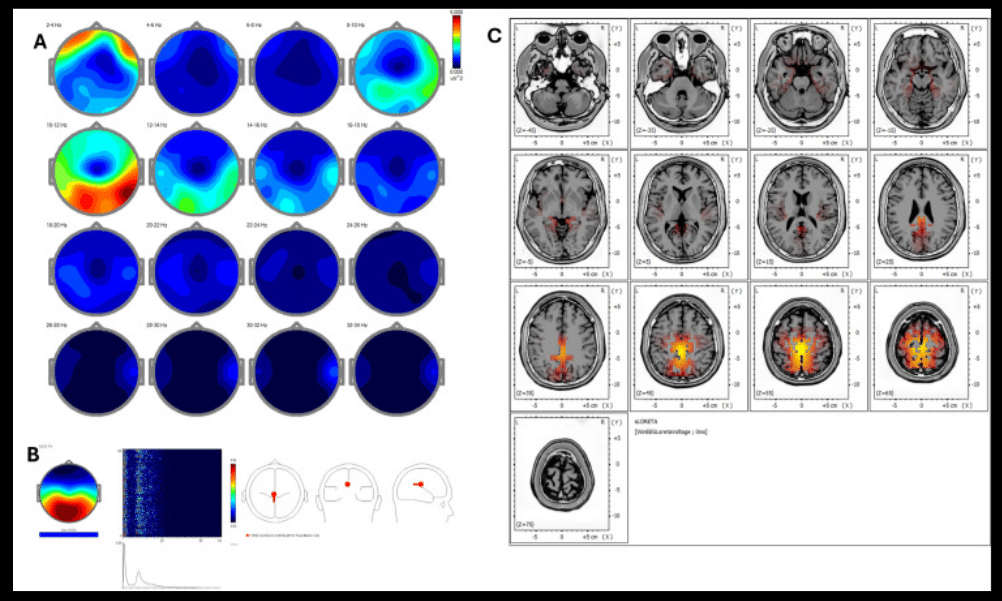

El estudio, de carácter retrospectivo, incluyó a cinco personas con exposición prolongada a estrés laboral. A través de 18 sesiones de REAC BWO-G, se evaluó la actividad cortical antes y después del tratamiento mediante técnicas avanzadas de análisis neurofisiológico (qEEG, ICA y sLORETA).

- Tendencias consistentes hacia una mayor simetría en bandas clave del EEG (delta, theta y alfa).

- Reorganización de la actividad cortical hacia redes asociadas con regulación emocional y cognición.

- Mejoras clínicas percibidas en estabilidad emocional, calidad del sueño y claridad mental.

- Patrones neurofisiológicos compatibles con una mayor resiliencia frente al estrés.

Los autores subrayan que estos hallazgos están en línea con la literatura científica que vincula el estrés crónico con alteraciones de conectividad cerebral. Aunque se reconoce la necesidad de estudios más amplios y controlados, los resultados sugieren que intervenciones no invasivas como REAC BWO-G podrían apoyar la recuperación funcional en contextos de estrés severo, sin efectos adversos reportados.